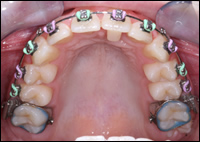

Fig 3 & 4: Upper and lower Schwartz Appliances were fabricated.